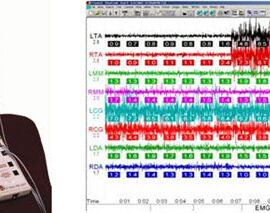

Реактивное тяжелое общее состояние организма, наступающее вскоре после травмы. Развивается в связи с нарушением нервной регуляции жизненных процессов и проявляется тяжелыми расстройствами гемодинамики, дыхания и обмена веществ. Этиология. Тяжелые ранения и повреждения, сопровождающиеся обширным размозжением тканей, ампутацией (отрыв) органов лица, массивными ушибами и сдавлениями челюстно- лицевой области, кровопотерей и кислородным […]